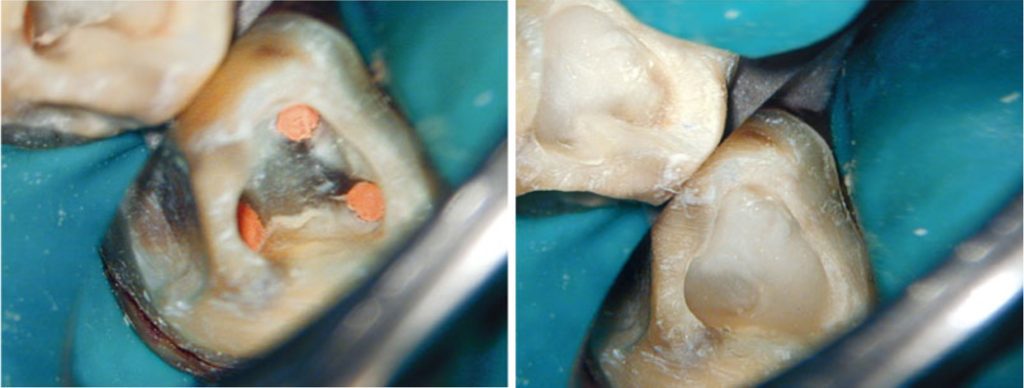

Cần loại bỏ mô sâu răng để ngăn ngừa rò rỉ và giảm nguy cơ mảnh ngà sâu chứa vi khuẩn đi vào ống tủy trong quá trình điều trị.

Điều trị nội nha bắt buộc phải được thực hiện dưới đê cao su.

Mở tủy

Nếu xoang mở tủy không đạt yêu cầu thì việc xác định và thăm dò ống tủy sẽ trở nên phức tạp hơn, tiên lượng điều trị sẽ bị ảnh hưởng do bị hạn chế làm sạch, khử khuẩn và trám bít.

Ngoài ra, còn có thể làm tăng nguy cơ gãy dụng cụ và tạo hình sai (ví dụ như lệch đường, tạo khấc), dẫn đến kiểm soát nhiễm khuẩn kém và cuối cùng là thất bại điều trị.

Thực tế thì hiếm khi xoang mở tủy có hình dạng hoàn toàn giống mô tả điển hình trong sách giáo khoa — tức là hình dạng của răng trẻ, chưa từng được phục hồi.

Trên thực tế thì kích thước buồng tủy và vị trí miệng ống tủy bị ảnh hưởng bởi lượng và vị trí ngà thứ cấp, ngà bậc ba được bồi đắp để đáp ứng với sâu răng, phục hồi, rò rỉ hoặc mòn răng theo thời gian.

Những tác động tích lũy này có thể làm thay đổi đáng kể kích thước và hình dạng buồng tủy.